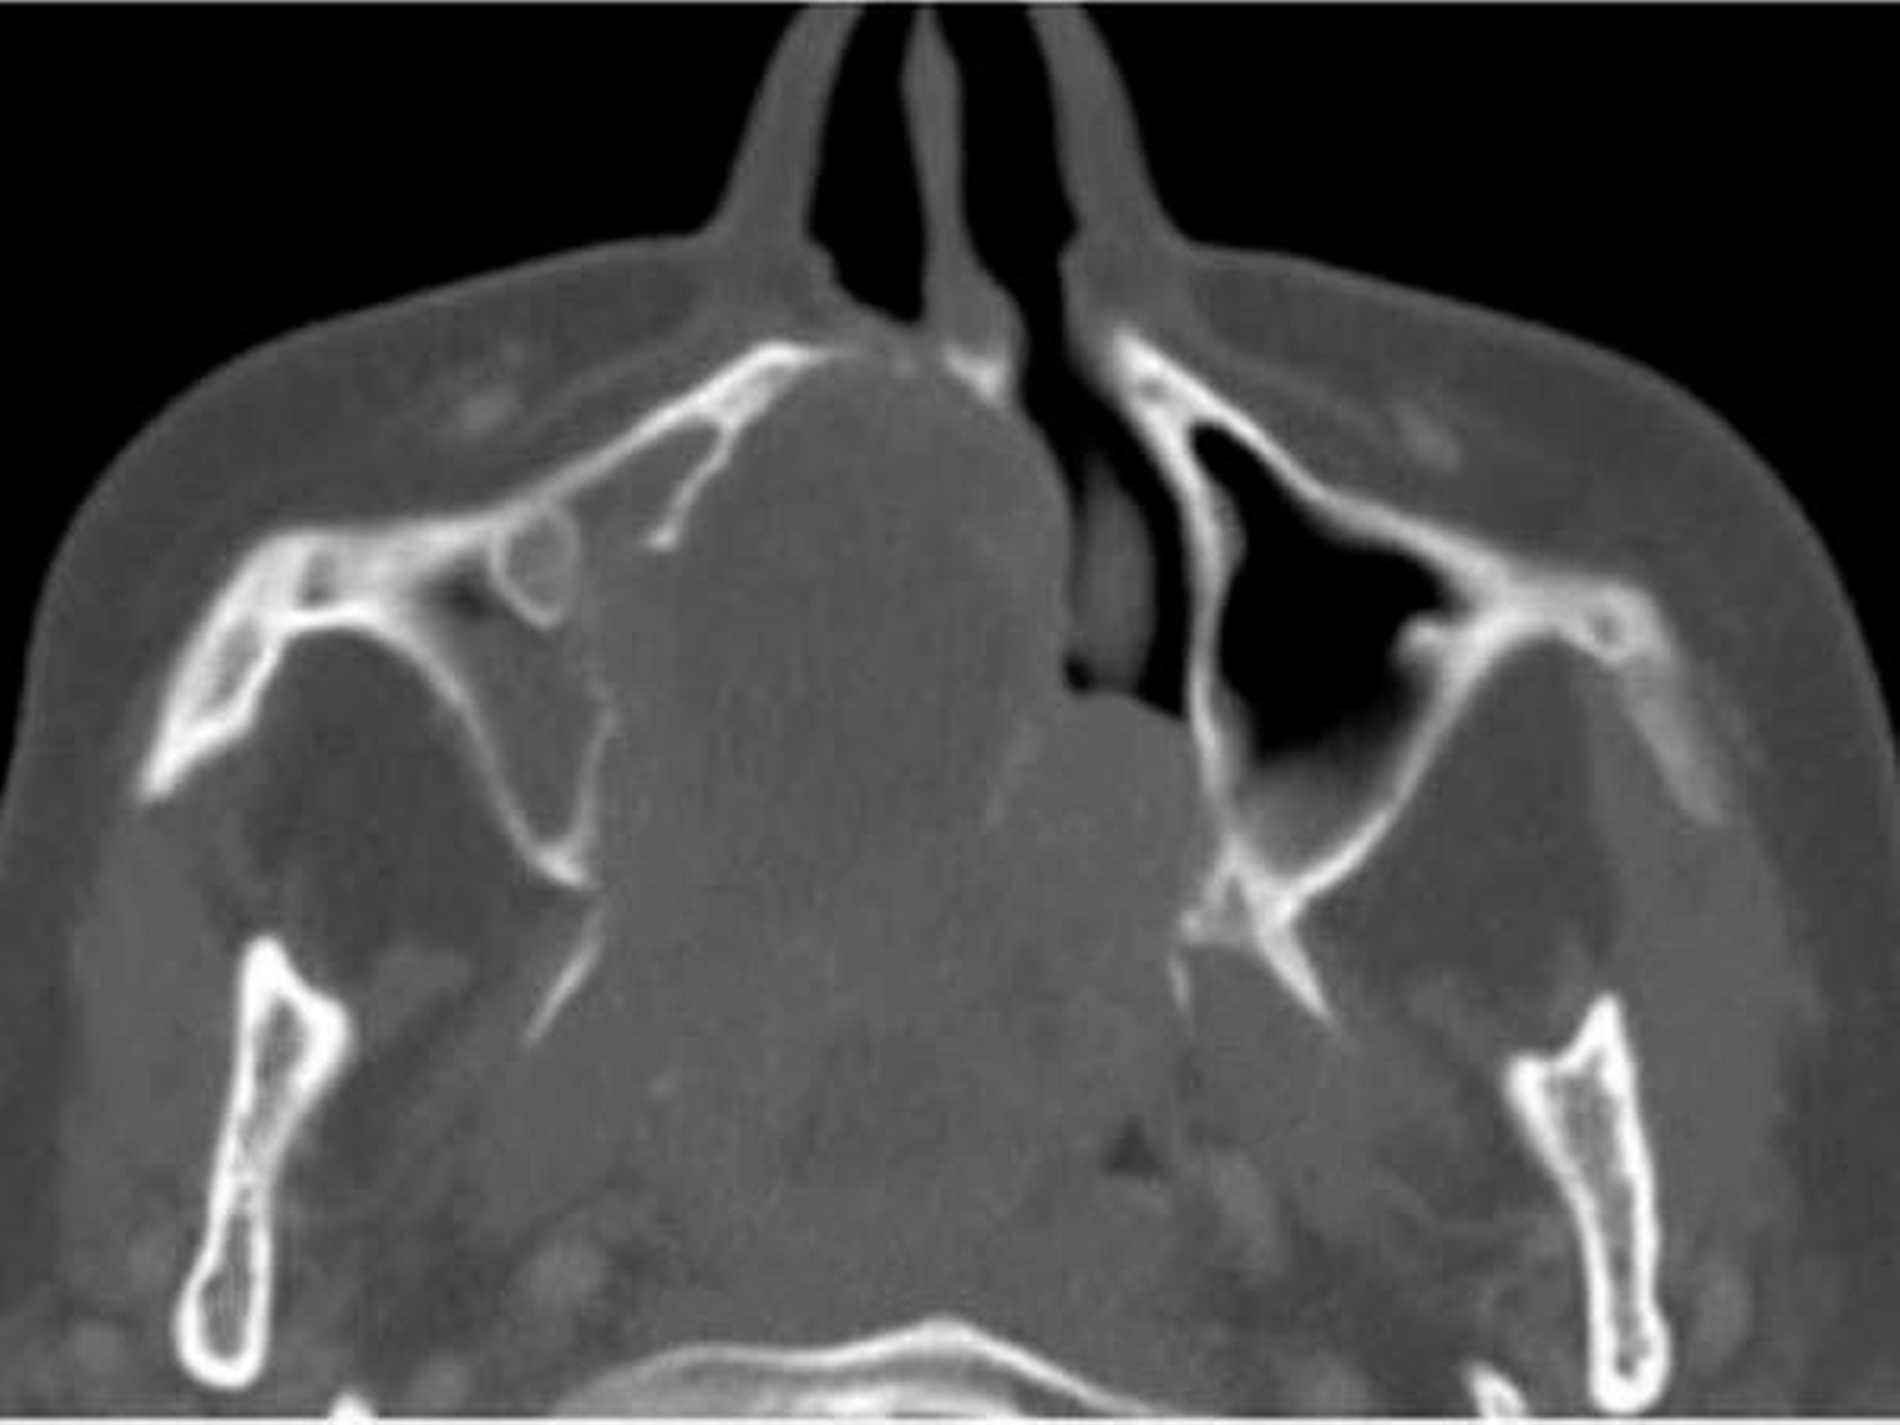

Die computertomografische Bildgebung zeigte eine inhomogene, kontrastmittelanreichernde und mittellinienüberschreitende Raumforderung im Bereich des Gaumens, die kaudal in die Mundhöhle und kranial in das Cavum nasi reichte. Die Größenausdehnung betrug circa axial 67 x 56 x kraniokaudal 52 mm.

Der Tumor wies multiple hypodense Anteile und einzelne Kalzifikationen auf. Die rechte Maxilla war distal der Regio 24 destruiert. Auch das Palatum durum et molle zeigten beidseits (rechtsbetont) Osteolysen bei primär verdrängendem Charakter auf. Der Nasopharynx war subtotal verlegt, die Uvula, der rechte M. constrictor pharyngis superior und beide Choanen nicht mehr abgrenzbar.

Der Tumor ragte durch die mediale Begrenzung des rechten Sinus maxillaris in die Nasenhaupthöhle mit einer hauchdünnen knöchernen Begrenzung. Rechts reichte die Raumforderung bis in die Fossa pterygoidea. Die Processus pterygoidei waren zentral aufgelöst. Rechtsseitig war die Anzahl der Lymphknoten in Level Ib und IIa/b vermehrt und moderat vergrößert, aber ohne klare Malignitätskriterien.